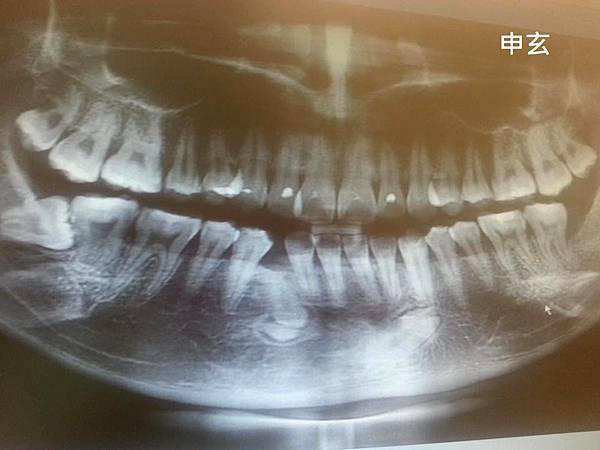

他說我下排缺牙的原因是因為有牙齒沒長出來,

而且還倒著長,要矯正一定要開刀弄出來,不然下排的牙齒關不起來,

矯正初估:智齒都要拔掉(當時還剩兩顆),矯正時間約1年~1年半

預估矯正流程:拔牙→做齒模→上矯正器(打骨釘)→拆矯正器→戴維持器